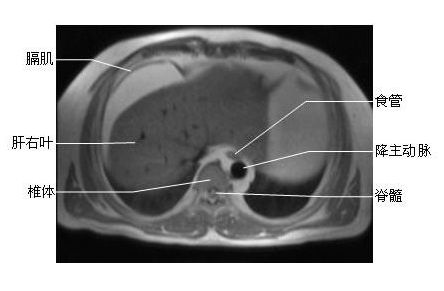

胸部横断面-MRI图片

胸部横断面- MRI图